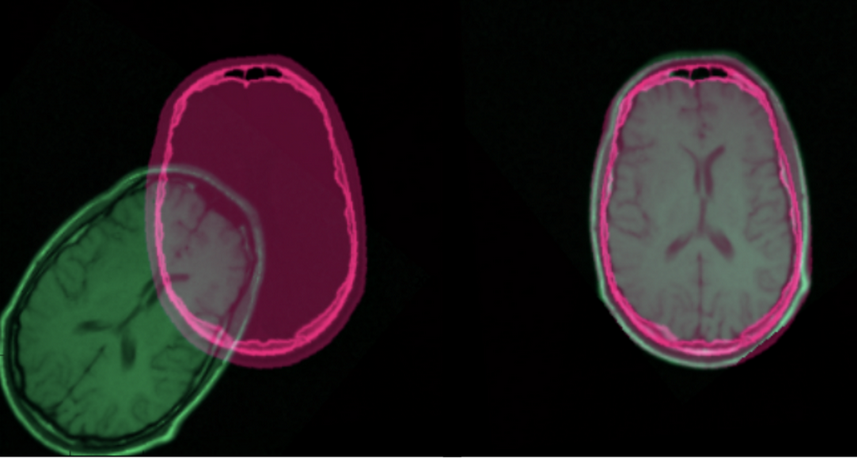

Medical image registration is a challenging area within medical image analysis. It aims at finding an optimal spatial transform between images so that they are spatially aligned into a uniform coordinate, which is crucial for some clinical applications such as image fusion. The registered images can be multi-modal and multi-dimensional, and registration can be either rigid or deformable. Traditionally, medical image registration is usually operated by clinicians. However, with the growth of the deep learning(DL) community in recent years, many deep learning methods have been proposed to tackle the image registration task. This blog post serves as an introduction to this area.

Figure 1. Image Registration Example